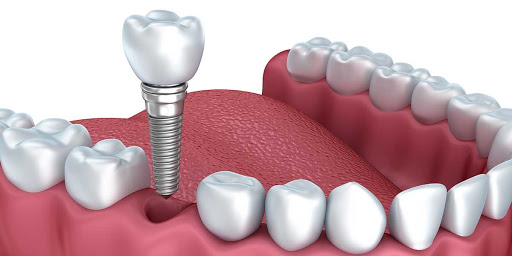

دانستنی های ایمپلنت

ایمپلنت چیست؟ایمپلنت مجموع قطعاتی است که با جراحی داخل فک ثابت می‌شوند روی آن دندان مصنوعی قرار می‌گیرد و در نهایت ظاه...